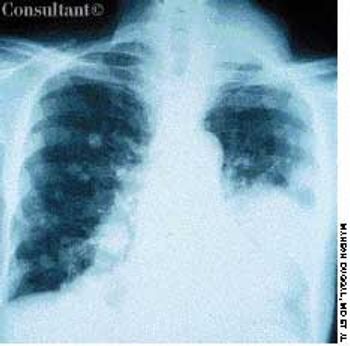

A 74-year-old man, who had been aware of a gradual increase in hat size over the past 3 years, complained of a mild headache and backache. His serum phosphatase level was 1,475 U/L (upper normal limit, 120 U/L). Skull films showed calvarial enlargement caused by thickening of the cortical tables, radiolucency in the frontal and occipital regions, and patchy osteosclerosis that produced a cotton-wool appearance.